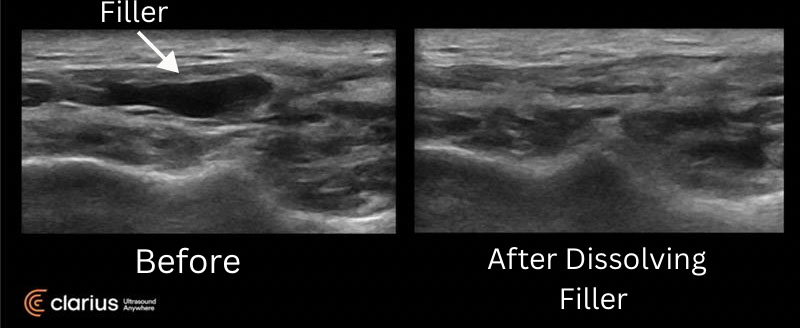

This patient came into the office for new nodules beneath the skin after having hyaluronic acid injected at another office. Here is what the filler looked like prior to injection of hylenex assisted with the Clarius US machine and afterwards. You can see the filler is no longer evident in the second image on the right.